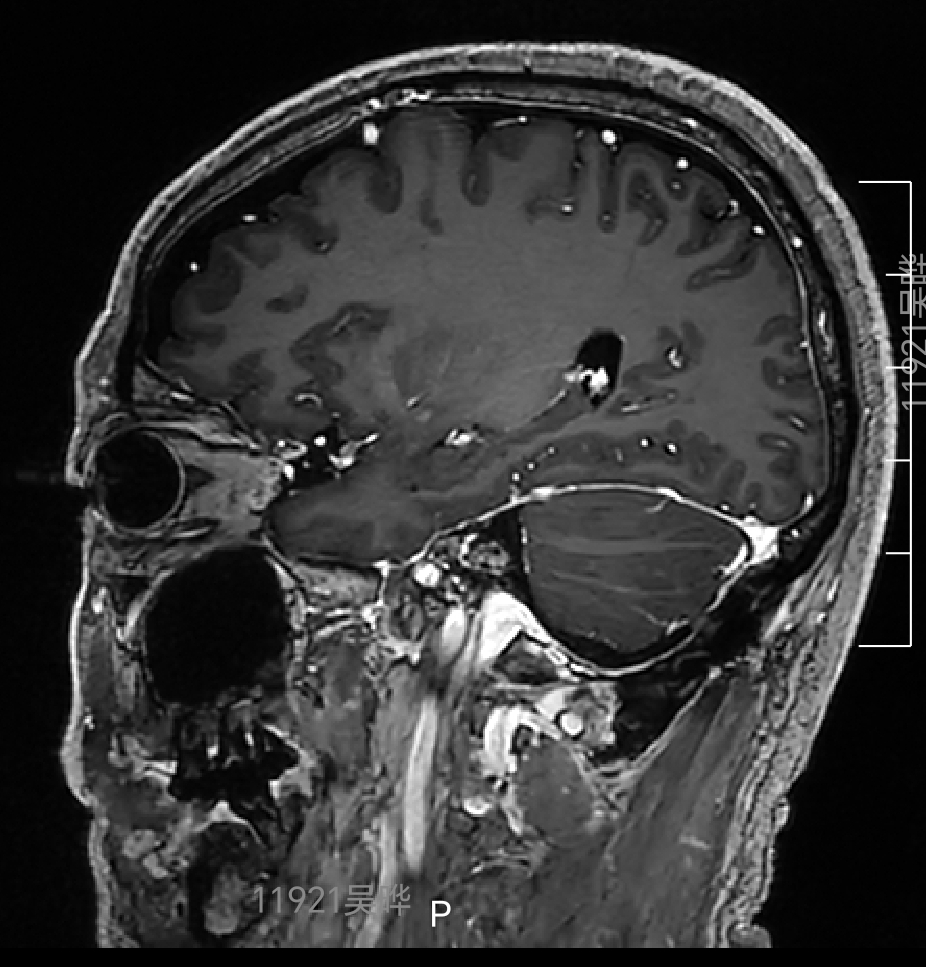

右侧桥小脑角3厘米占位,内听道扩大,肿瘤血供丰富,上方达天幕,与脑干关系密切,蛛网膜间隙不明显,颈静脉球相对高位,诊断考虑:右侧前庭神经鞘瘤(听神经瘤)

术后磁共振增强复查提示肿瘤全切,内听道内肿瘤无残留

内听道内高信号影为填塞的脂肪块